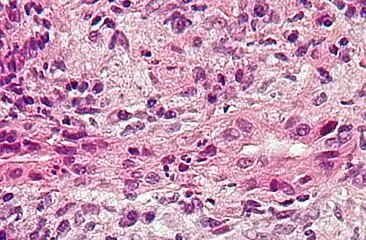

Ground glass hepatocytes Primary biliary cirrhosis

Primary biliary cirrhosis Budd–Chiari syndrome

- Primary biliary cirrhosis is a serious autoimmune disease of the bile capillaries.[17]